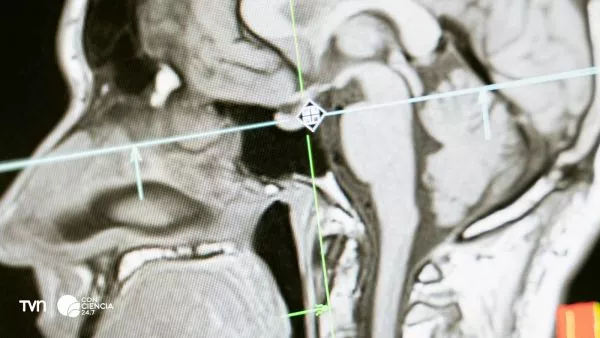

Científicos identifican cinco etapas en la evolución del cerebro humano, con cambios clave a los 9, 32, 66 y 83 años, según un estudio publicado en Nature Communications.